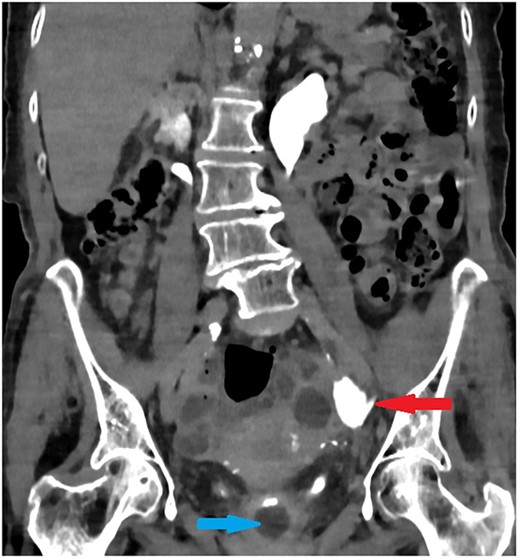

Luo et al. published a review included 23 cases of urethral catheter inadvertently placed into the ureter, 5 cases were caused by supra-pubic catheter [7]. Only three cases (13%) needed surgical repair (Fig. 4). Most of these cases had LTC secondary to neurogenic bladder, with female predominance (3:1). LTC might lead to contracted bladder, facilitating LTC to pass into the ureter in the presence of VUR. In addition, the short urethra in female might increase the risk of ureteric placement of LTC.

Luo et al. review: Only three cases (~13%) needed surgical repair. Three cases needed endoscopic deflation of the catheter balloon. Four cases needed urinary diversion, three with JJ ureteric stent and one with nephrostomy due to failed ureteric stenting. Thirteen cases were treated conservatively with simple catheter replacement.